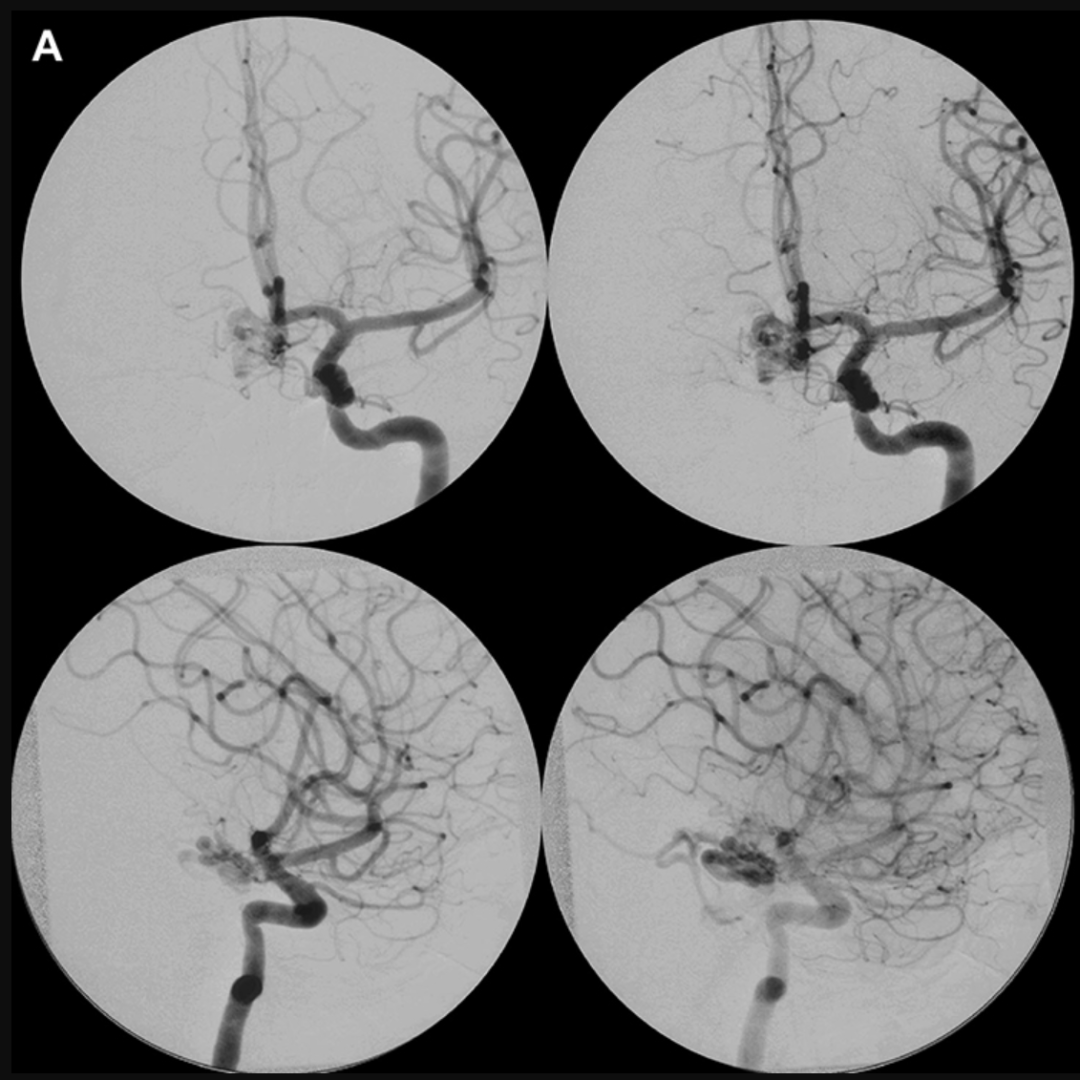

随后,朱莉去医院做了更深入的检查,脑血管造影揭示了病灶的全貌:一团异常血管网盘踞在视交叉与鞍旁区——人类视觉传导的“十字路口”。它由三条危险血管供血:左侧垂体上动脉、右侧后交通动脉的隐秘分支,以及双侧脉络膜前动脉(图1)。根据国际通用的Spetzler-Martin分级(II级)和Lawton-Young分级(III级),这预示着中等手术风险。

术前影像